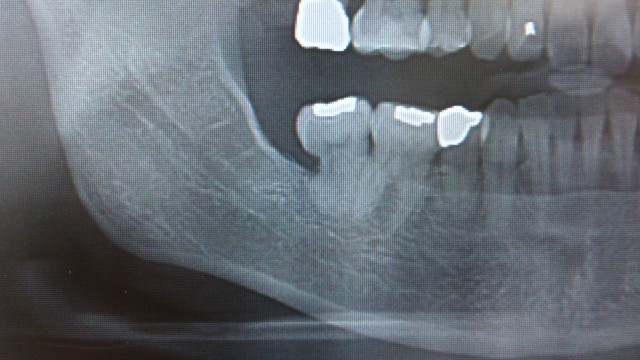

手前の歯は虫歯にはなっていませんが、

重度の歯周病になって骨が溶けてしまった方。

ガッツリ骨溶けました。顎をぶつけたら、骨折しそうです。